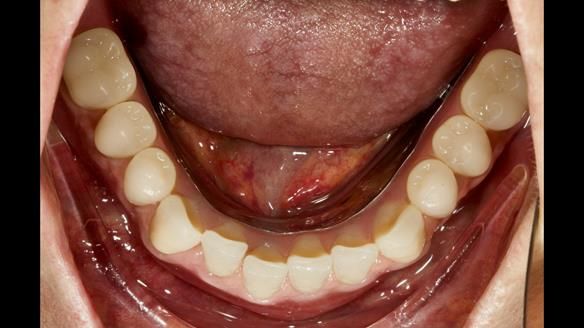

This newsletter describes in step by step detail the provision of a lower implant supported metal based complete denture with three dental implants positioned in the anterior mandible. The upper arch was restored with a metal based complete upper denture.

Mary had 3 dental implants placed in the anterior mandible 10 years previously with new complete dentures. These were successful for a time. The dentures were replaced a few years later. Mary was never pleased with the new lower denture as they did not fit the implants properly. This patient was referred to me from Ireland, to my practice in Garstang, England.

- Locator attachments not engaging the housings in the lower denture.

- Suboptimally shaped dentures with poor tissue fit resulting in rocking of the dentures.

- Bland aesthetics.